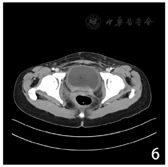

患者治疗结束后无特殊不适,每3个月至我院复查,末次复查时间为2022年9月6日,妇科检查呈术后改变,NSE、SCC未见异常,其余影像学检查均未见明显复发和转移征象(图6)。